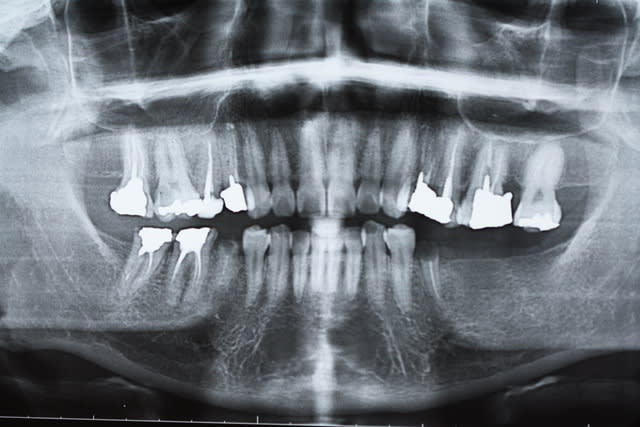

Bon j'ai un vivier , il y a de tout . Remarquons qu'il n'y a aucuns foyers apicaux , il y a de tout sauf ça . Je me suis toujours fait la réflexion qu'avec les contacts étroits dents-os , la dentisterie souvent est chanceuse...

Si sous la 47 (pas jolie cette pano)